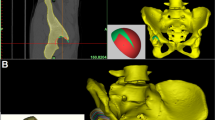

The CT imaging data of bilateral hip joints of the patient (Fig. 2A) were imported into Mimics 20.0 software (Materialise, Belgium) workstation in DICOM format for three-dimensional modeling (Fig. 2B). Through a collaborative effort between engineers and surgical physicians, the true acetabular position and acetabular cup model for the prosthesis were calculated (Fig. 3A). Parameters such as bone defect shape, size, etc., were measured, and the model of the Augments prosthesis was designed, followed by determining the placement position of the Augments prosthesis (Fig. 3B and C) and selecting the femoral prosthesis model (Fig. 3D).

Design and Positioning of Acetabular and Augments Prostheses, and Determination of Femoral Implant Size. (A): Original acetabular positioning and model simulation for the patient. (B): Assessment of bone defect and simulation of personalized Augments prosthesis. (C): Simulation positioning of acetabular and Augments prostheses in coronal, transverse, and sagittal planes. (D): Measurement of femoral medullary canal thickness for determination of femoral implant size.